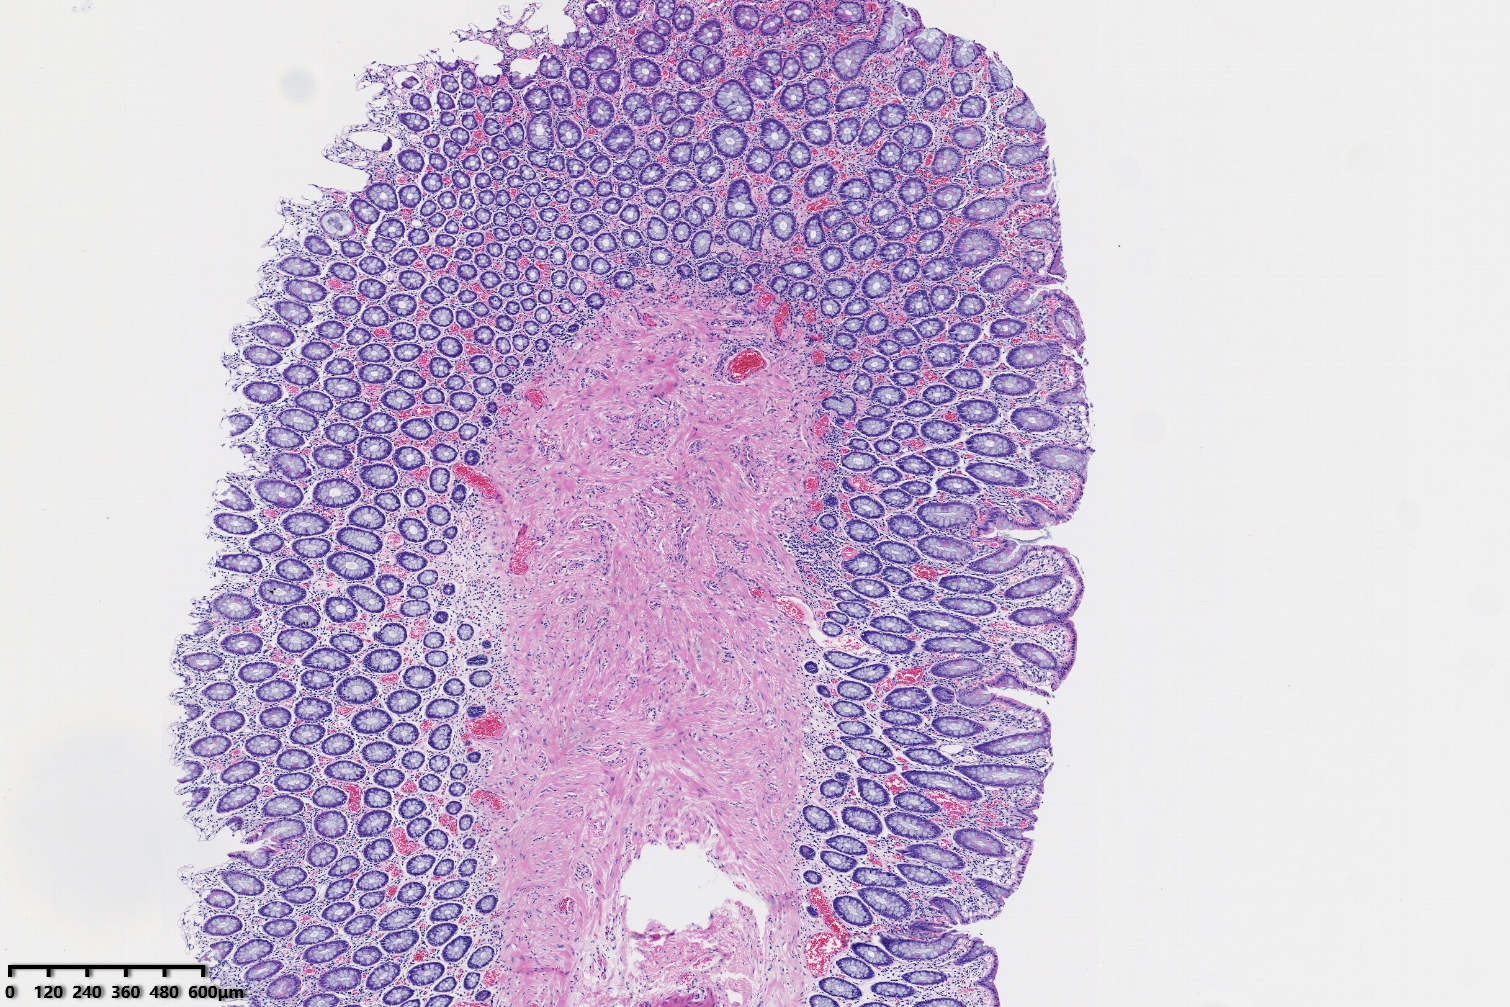

结肠息肉,请教老师们发什么息肉妥当?

结肠息肉

炎性息肉(黏膜脱垂相关息肉)

形态符合粘膜脱垂相关息肉。